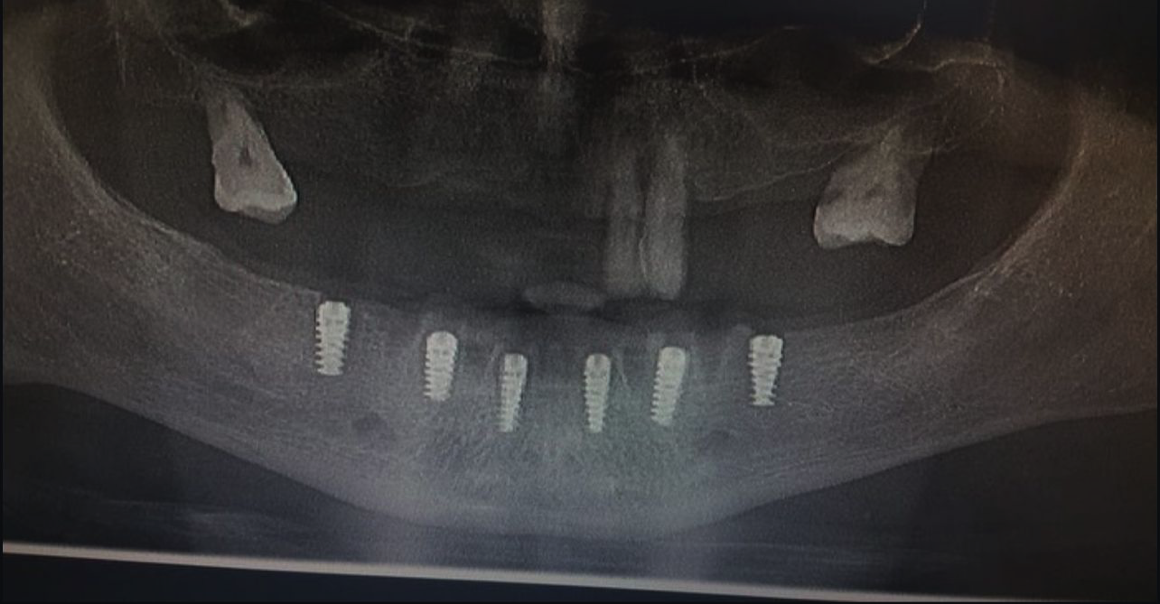

MPI All-In System®, modern dental implantolojinin tüm gereksinimlerini tek bir gövdede toplar. İster dar kretler ister sınırlı kemik yüksekliği olsun; All-In teknolojisi, hekime en zorlu anatomik koşullarda bile tam kontrol imkanı tanır.

Sinüs lifting veya kemik ogmentasyonu gibi ileri cerrahi müdahalelere gerek kalmadan, sınırlı dikey kemik mesafesinde güvenli ve estetik sonuçlar sağlar. Daha az cerrahi müdahale, daha hızlı iyileşme süreci ve yüksek hasta memnuniyeti.

Karmaşık vakalar için tek bir mükemmel çözüm: MPI All-In System®. Modern dental implantolojinin sınırlarını zorlayan bu sistem, her kemik tipinde yüksek performans ve klinik güven sunar.